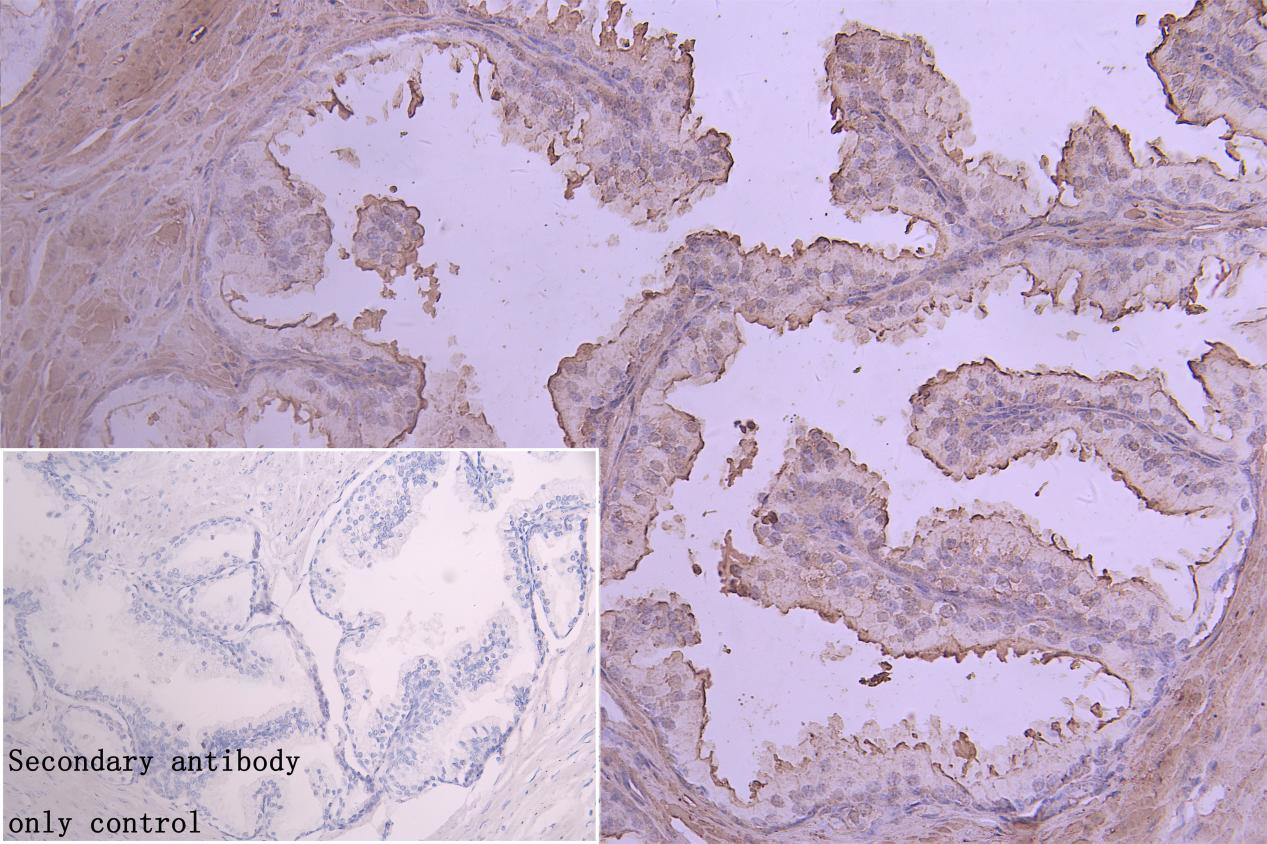

IHC image of CSB-PA822219LA01HU diluted at 1:20 and staining in paraffin-embedded human prostate cancer performed on a Leica BondTM system. After dewaxing and hydration, antigen retrieval was mediated by high pressure in a citrate buffer (pH 6.0). Section was blocked with 10% normal goat serum 30min at RT. Then primary antibody (1% BSA) was incubated at 4°C overnight. The primary is detected by a Goat anti-rabbit polymer IgG labeled by HRP and visualized using 0.05% DAB. Secondary antibody only control: uses 1% BSA instead of primary antibody